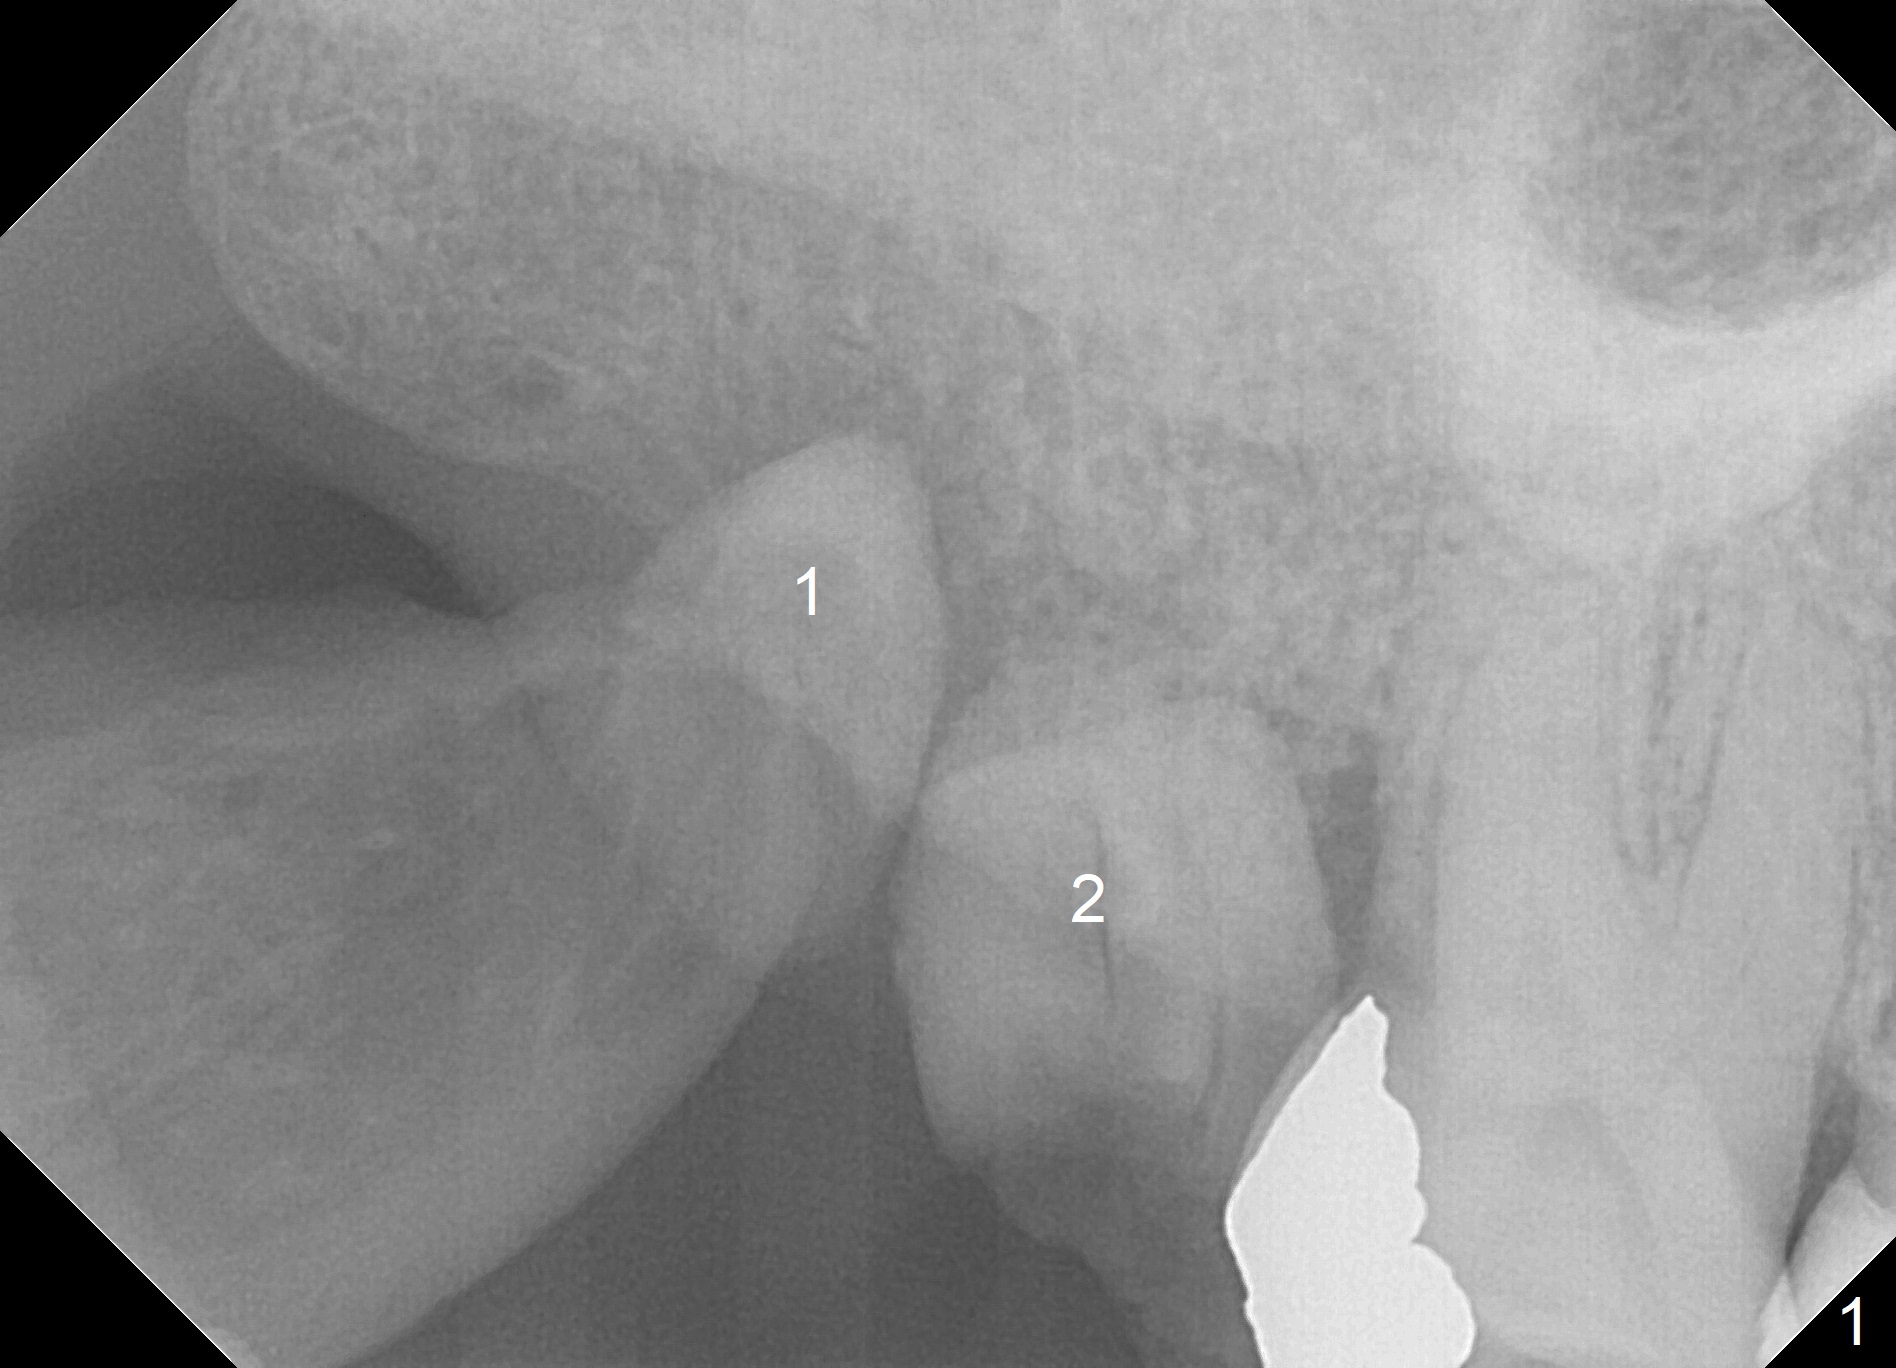

A 60-year-old woman requests extraction of the upper right 2nd and third molars and one implant (Fig.1). Although there is no problem of bone height, the intermaxillary vertical space is limited (data not shown). After implant (Fig.2) and abutment placement, the opposing tooth may need heavy reduction. Pay attention to implant trajectory so that a straight abutment will be used to avoid restorative complication (screw loosening).